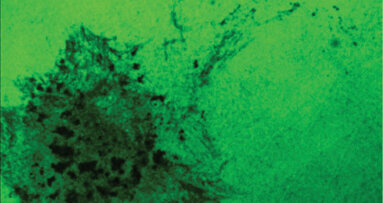

ALEXANDRIA, VA, USA: Defined sets of factors can reprogramme human cells to induced pluripotent stem (iPS) cells. However, many types of human cells are not easily accessible to minimally invasive procedures. In a paper published in the International and American Associations for Dental Research’s Journal of Dental Research, researchers from the Gifu University Graduate School of Medicine and Kyoto University evaluate dental pulp cells as an optimal source of iPS cells, since they are easily obtained from extracted teeth and can be expanded under simple culture conditions.

From all six cell lines tested with the conventional three or four reprogramming factors, iPS cells were effectively established from five lines. Furthermore, determination of the human leukocyte antigen (HLA) types of 107 DPC lines revealed two lines homozygous for all three HLA loci and showed that if an iPS bank is established from these initial pools, the bank will cover approximately 20 per cent of the Japanese population with a perfect match.

Analysis of these data demonstrates the promising potential of dental pulp cell collections as a source of cell banks for use in regenerative medicine. Direct reprogramming of patients’ somatic cells would allow for cell transplantation therapy free from immune-mediated rejection. An alternative approach is to establish an iPS cell bank consisting of various HLA types. Safety issues must be considered as to which types of somatic cells should be used for such iPS cell banks.